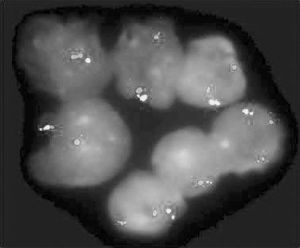

何杰金病何杰金病(hodgkin′sdisease)又名淋巴網狀細胞肉瘤是一種慢性進行性、無痛的淋巴組織腫瘤,其原發瘤多呈離心性分布,起源於一個或一組淋巴結,以原發於頸淋巴結者較多見,逐漸蔓延至鄰近的淋巴結,然後侵犯脾、肝、骨髓和肺等組織。由於發病的部位不同,其臨床表現多種多樣。5歲以前很少發病,5歲以後逐漸增多,青春期發病率明顯增多,15~34歲為高峰。發病者男性多於女性。男女比例在5~11歲為3∶1,19~19歲為1.5∶1。

最早的表現多是淺表淋巴結呈無痛性進行性腫大,常缺乏全身症狀,進展較慢。約有60%原發於頸淋巴結,原發於鎖骨上、腑下及腹股溝淋巴結的較少見。初起時,淋巴結柔軟,彼此不粘連,無觸痛。後期增大迅速,可粘連成一巨大腫塊。其特點為臨近組織無炎症,不能用以解釋淋巴結腫大的原因。腫大的淋巴結可以引起局部壓迫症狀,如縱隔淋巴結腫大壓迫氣管支氣管,引起乾咳。無原因的腹痛可由於後腹膜淋巴結腫大所致。全身症狀可有低熱,或呈特徵性回歸熱型,即高熱數天后,可有幾天或幾周的無熱期(pel-ebsteinfever)。常有食慾減退、噁心、盜汗和體重減輕,這些症狀當病灶局限時常不出現。皮膚搔癢是成人常見的症狀,在小兒極少見,甚至在全

何杰金病身廣泛臟器受侵時也不出現。約有1/4的患兒在診斷時已轉移到淋巴結以外的組織,多見於脾、肝、肺或骨及骨髓。肺部浸潤的x線改變多為絨毛狀滲出性改變,與真菌感染不易區別,多有呼吸加快和發熱,甚至出現呼吸功能衰竭。肝臟受累,可出現肝內膽管梗阻症狀,肝臟中度腫大,鞏膜黃染,血清直接與間接膽紅素和鹼性磷酸酶增高。骨髓浸潤則出現中性粒細胞、血小板減少和貧血。消化道受累可發生黏膜潰瘍和消化道出血。淋巴瘤發生在脊髓腔硬膜外,可引起壓迫症狀。此外,亦可出現各種免疫功能紊亂如免疫性溶血,血小板減少或腎病綜合徵。